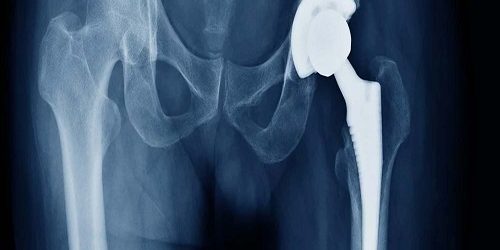

Total kalça artroplastisi, kalça ekleminin kronik ağrı, kısıtlı hareketlilik ve diğer sorunlara neden olan hastalıklı veya yıpranmış kısımlarını değiştirmek için cerrahi bir prosedürdür. Bu işlem, kalça ekleminin doğal yapılarını yerine titanyum, seramik veya plastik gibi dayanıklı ve biyolojik olarak uyumlu malzemelerden yapılmış protezlerle değiştirir.

Protez Uygulaması: Total kalça artroplastisi sırasında, cerrah hasarlı kemik ve dokuları çıkarır ve bunların yerine protez bileşenleri yerleştirir. Bu bileşenler genellikle kalça kemiğinin üst kısmına bir top protezi (femur başı), kalça kemiğinin iç kısmına bir gövde protezi (aseta) ve pelvis kemiğine bir yatak protezi (aseta) içerir.

Protez Malzemeleri: Total Kalça Artroplastisi | Protezler genellikle titanyum, seramik veya plastikten yapılır. Titanyum dayanıklıdır ve kemikle iyi bir şekilde bütünleşirken, seramik aşınmaya dayanıklıdır ve plastik ise sürtünmeyi azaltır.

Protez Yerleştirme:

• Protez bileşenleri, titanyum veya seramikten yapılmış metal ve plastik parçalardan oluşur.

• Femur başı ve asetabulumda uygun boyutta protezler yerleştirilir.

• Protezler, kemikle sıkıca birleştirilir ve çoğunlukla kemik çimento veya pres fit ile sabitlenir.